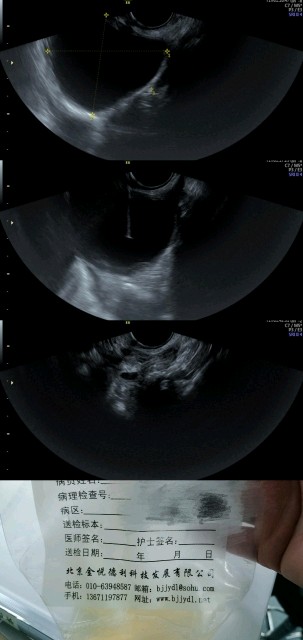

这个患者53岁,囊肿7cm左右,发现已经有14年之久了,之前有痛经,VAS5分。术前评估CA125轻度升高,囊肿内无实性部分,既往患者有痛经,超声评估怀疑有可能是巧囊,但是穿刺发现囊肿液体是淡黄色的清亮液体,这也就间接证明了囊肿不是巧囊,但是因为没有病理,我们只能大概判断囊肿可能是卵巢浆液性囊腺瘤或单纯囊肿导致的问题,穿刺固化对于这样的囊肿也是具有治疗价值。